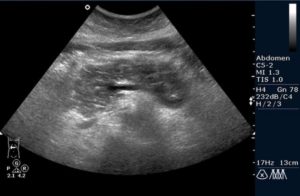

Но более информативным методом диагностики является ультразвуковое исследование. Одним из важных диагностических признаков в этом случае являются диффузные изменения железы. Контуры органа при этом могут быть неровными, а ее размеры, как правило, находятся в пределах нормы.

Фиброз поджелудочной железы не является самостоятельным заболеванием. Этим термином обозначают патологические изменения органа, которые обычно являются признаком хронического панкреатита. Фиброз определяется на УЗИ. Как правило, он не сопровождается симптомами, поэтому становится случайной находкой врачей при плановом обследовании пациента.

Клинических признаков фиброз не имеет. Его можно увидеть на УЗИ. Замещение паренхимы соединительной тканью видит патологоанатом при вскрытии больного. А вот определить фиброз по симптомам нельзя.

Виден ли фиброз печени на УЗИ?

При проведении диагностики получить однозначный ответ на вопрос о том виден ли фиброз печени на УЗИ невозможно. Поскольку изменение эхогенности и структуры органа может происходить при других заболеваниях, его можно легко спутать с другой болезнью.

Как определить фиброз по УЗИ?

Зачем проводят ультразвуковую диагностику и как определить фиброз по УЗИ, спросите вы? Распознать патологический процесс в паренхиматозном органе можно только по косвенным признакам. У пациентов с дегенеративным заболеванием печени наблюдается: асцит, изменение кровотока в воротной вене и увеличение размеров самого органа.

Важный метод диагностики фиброза поджелудочной железы – ультразвуковое исследование органов брюшной полости (УЗИ брюшной полости). Определяется диффузное повышение эхогенности органа, структура неоднородная, размеры уменьшены; возможно выявление расширения вирсунгова протока.

Более информативна эндоскопическая ультросонография, которая позволяет выявить линейные тяжистые включения разной протяженности и формы, бугристость контуров, гиперэхогенность паренхимы. При проведении ЭРХПГ выявляются изменения протокового аппарата, вызванные образованием рубцов.